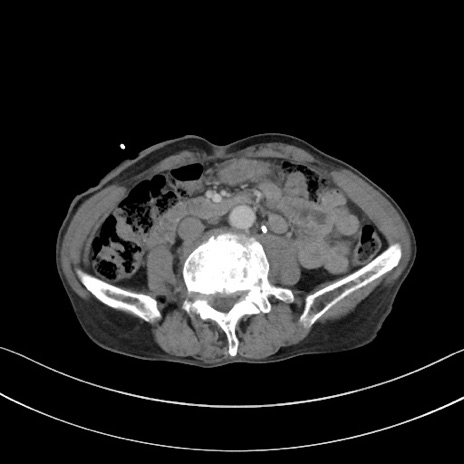

症例3(横断像)

【症例】 70歳代男性

【主訴】右鼠径部腫瘤、疼痛

【現病歴】本日朝より上記主訴あり、受診。

【既往歴】膀胱癌にて膀胱全摘、両側尿管皮膚瘻

【データ】WBC 5600、CRP 0.56